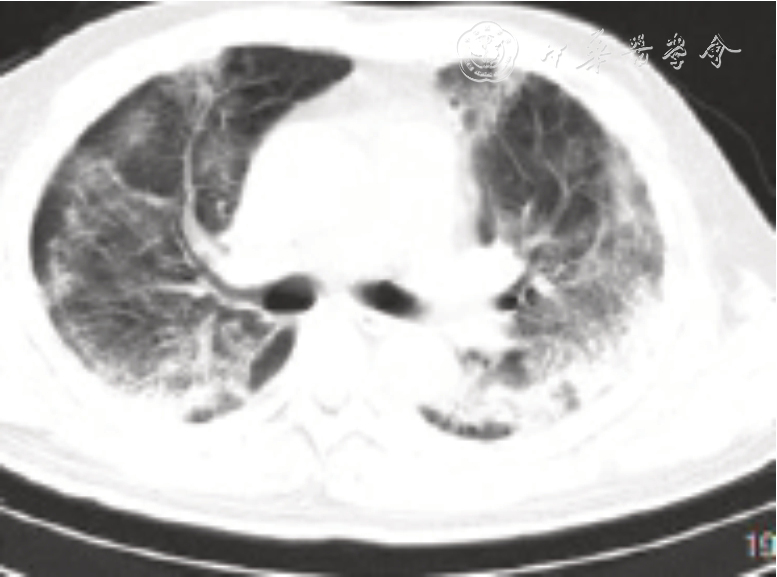

图2 新型冠状病毒肺炎患者早期胸膜下淡斑片状影